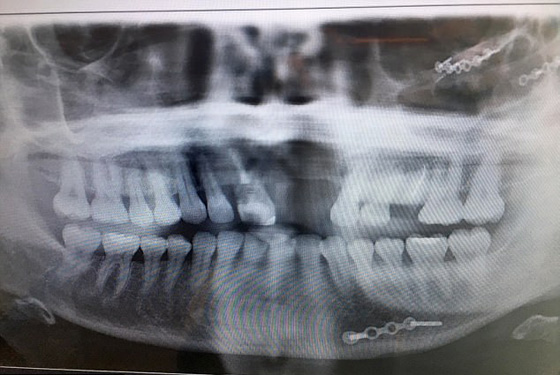

وتورم رأس الفتاة من جراء الحادث ليصبح بحجم كرة السلة. وبسبب تشوه وجهها بالكامل، خشي الأطباء أن تبقى ساندرا بدون أسنان لفترة طويلة، ونتيجة لذلك بدأت ساندرا التفكير على نحو متزايد بالانتحار. وقالت ساندرا "بعد الحادث فكرت بالموت كل يوم، لقد كرهت حياتي وأنا أخفي وجهي من العالم لمدة ست سنوات. وأضافت "أسناني تؤلمني بشكل فظيع، ووصل الحد للتحقق من وجود أسناني صباح كل يوم أمام المرآة. وسامحت ساندرا الشاب المخمور الذي تسبب بالحادث ولها بالمعاناة، والذي كان يبلغ حين وقوع الحادث 18 عاما، وهو الآن متزوج ولديه طفلة ويعيش حياته الطبيعية.